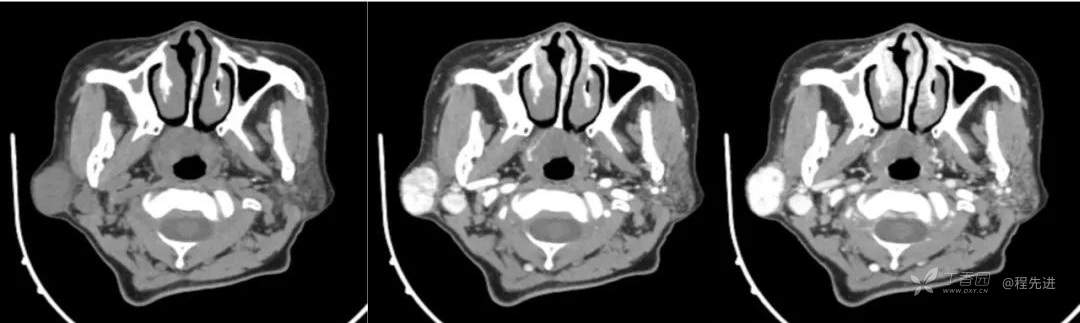

简要病史:发现右侧耳下肿物12年,不痛,缓慢生长

既往史:19年前因右侧腮腺肿物在当地医院行手术(具体不详),17年前因右侧腮腺肿物复发再次在当地医院手术(具体不详)

体格检查:右侧耳下可扪及大小约3*3cm肿物,质地中,边界清,活动可,无明显压痛。颈部未扪及明显肿大淋巴结